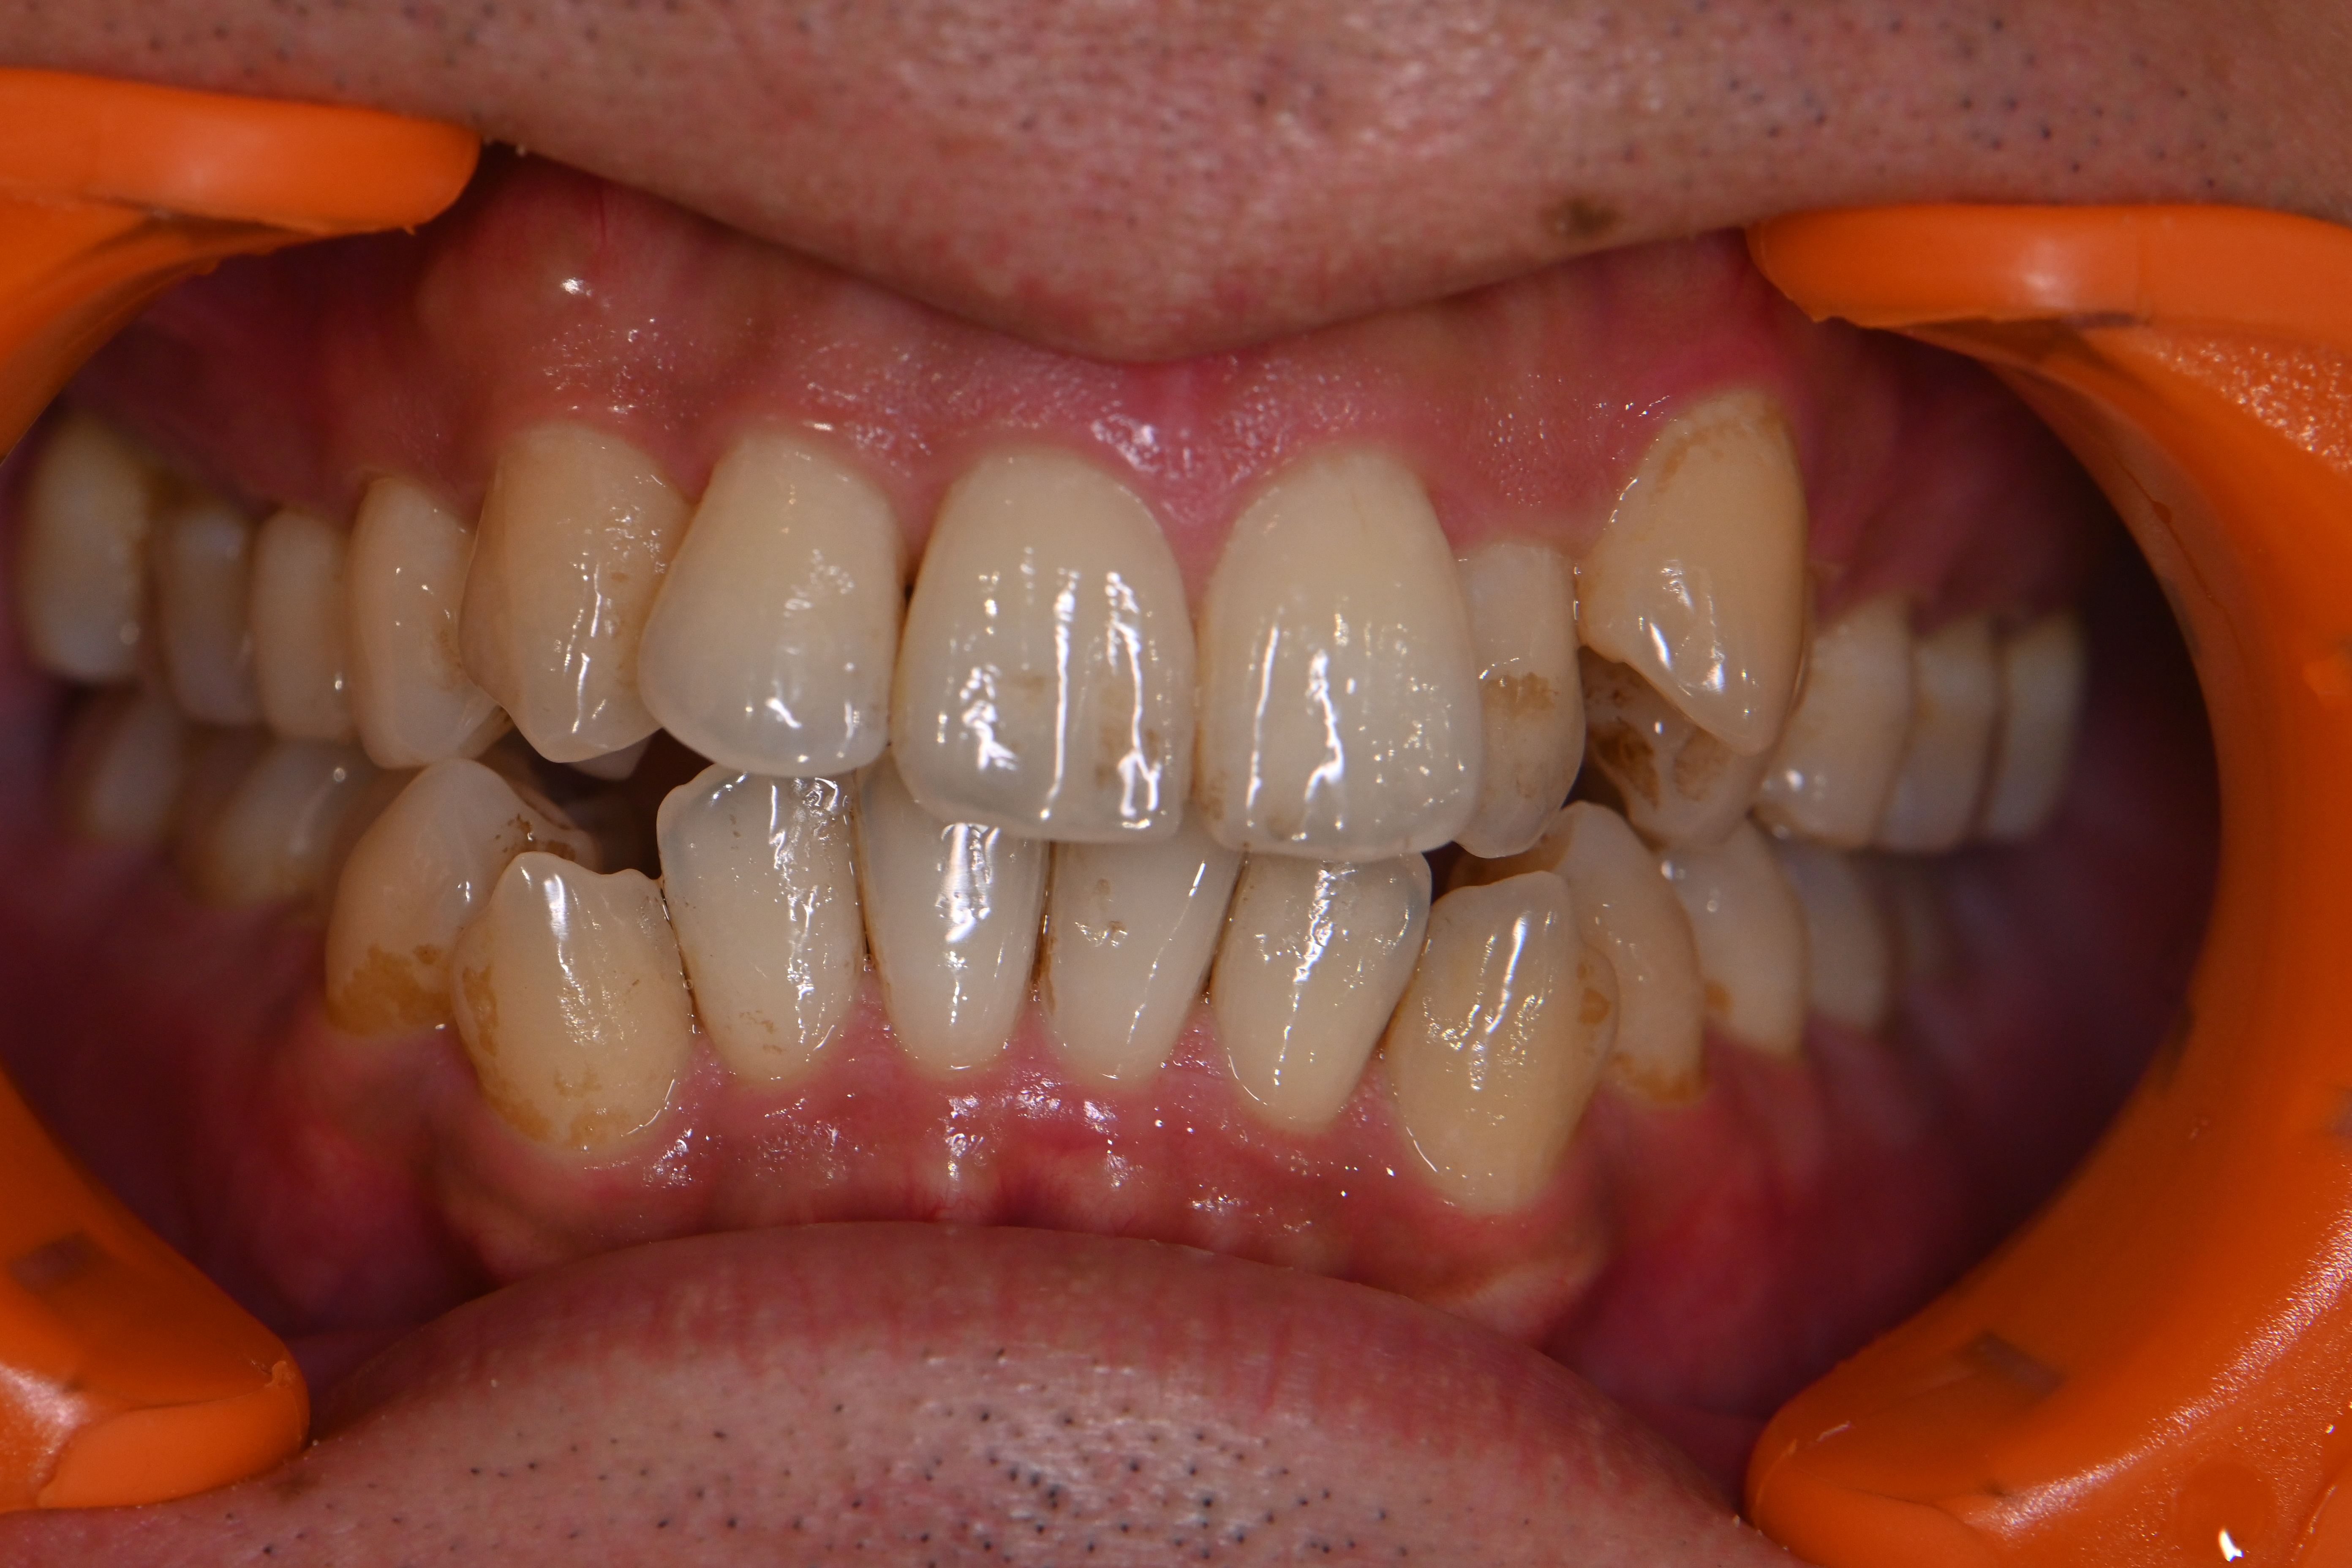

今回は全体的に着色が気になる方の症例です。

他の歯医者さんで以前からエアフローで着色を除去されてきた患者様ですが、前回してから半年期間が空いてしまったら再度着色が目立つようになったのこと💦

細かい着色をエアフローでしっかり除去して、仕上げにリナメル(歯の細かい傷を埋めてくれる)を塗布しました✨

場所によっては分厚い磨き残しがあり、そこに着色していた箇所もあったため歯磨き指導も一緒にさせていただきました。